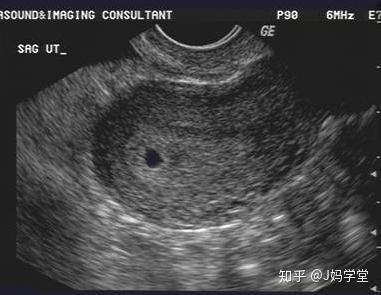

怀孕4周左右,B超看不到胎囊 患者信息:女 30岁 广东 珠海 病情描述 (发病时间、主要症状等): 怀孕4周,B超看不到胎囊,医生说有可能宫外孕,但是下腹一直没疼痛,也没出血! 月经最后一天是1254但是只有1264那一天同房一次就怀孕了,这样应该是怎么 9周 2.15厘米 此时胎囊几乎占满宫腔,胎儿各部表现更清晰,胎盘开始出现。 10周 2.厘米 这个时段胎囊开始消失,胎儿各器官均已形成,胎儿活跃在羊水中。 11周 3.62厘米 胎儿各器官进一步发育,胎盘发育,b超可见胎囊完全消失,胎盘清晰可见。 12周 458厘米 胎儿各脏器趋 6周 4,hcg,只有少许胎芽,没有胎心 查看 回复 29 t 发表于 2211 1645 来自疯狂造人 举报 29 楼主 直达 楼 谢赞,祝你好孕快快来 已邀请用户 : (此提示只有您可以看到,其他用户无法查看)

怀孕4周时,受精卵才着床成功; 怀孕5周时,受精卵着床成功后一边快速进行细胞分裂,一边向四周扩展,而这些细胞将会形成羊膜和血管包裹住 卵黄囊,胎儿就是从卵黄囊开始发育的。 在卵黄囊的外面是孕囊,孕囊是原始的胎盘组织。 所以, 一般在怀孕56周,可以做B超看到孕囊和卵黄囊,月经规律的女性,最早在怀孕35天时可以通过阴超看到孕囊; 怀孕67周时,可以通过B超看到胎3 怀孕5周孕囊大小多少是正常的 1、4周:胎儿只有02厘米。 受精卵刚完成着床,羊膜腔才形成,体积很小。 超声还看不清妊娠迹象。 2、5周:胎儿长到04厘米,进入了胚胎期,羊膜腔扩大,原始心血管出现,可有搏动。 B超可看见小胎囊,胎囊约占宫腔不到1胎芽特征 怀孕的第一个月为胎芽期,新生命在此期的成长速度是其一生中最快的。 妊娠第二周末精卵结合,受精后约4天,分裂成细胞团的精卵沿着 输卵管 到达子宫。 第三周,细胞团脱去外膜,为着床作准备。 第四周,胚泡已牢固地植入子宫里。 在这个